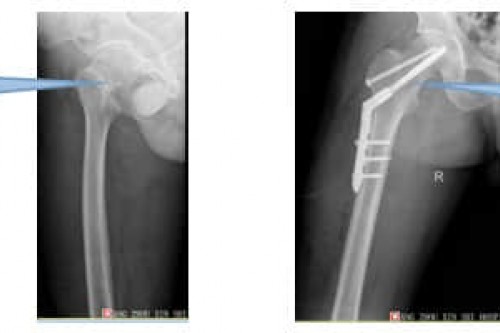

看骨科就到广东药科大学广州复星禅诚医院真实案例展示 骨科以技术质量创品牌,诚信服务求发展为宗旨,不断攻克技术难关,取得快速发展,治疗大量创伤、关节、手足外科、脊柱疾病病人,效果良好,广获百姓好评:看骨科就到广东药科大学广州复星禅诚医院。 以下是部分真实案例展示: 案例一 陈先生,男